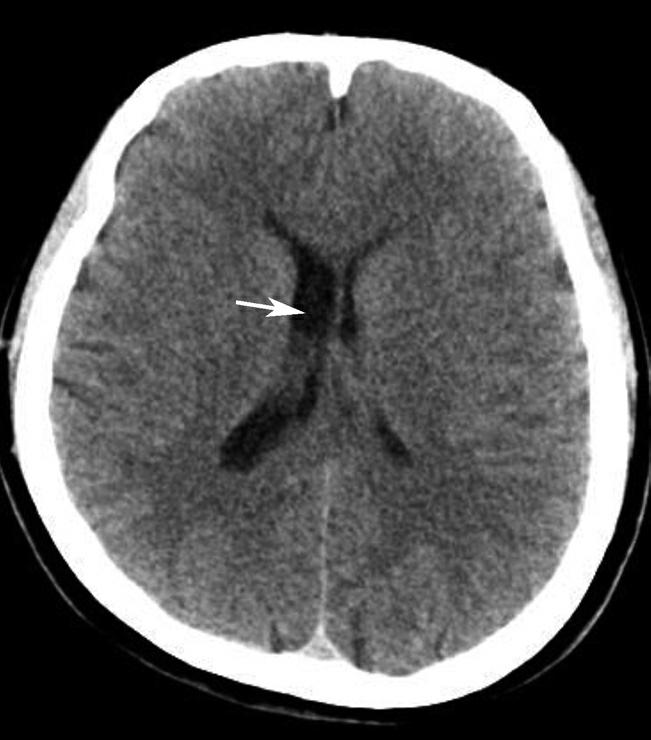

第三脑室正常成人前后径约12mm,左右宽约5mm,上下径也约为12mm。侧脑室后角两侧有时大小不等,右侧后角上下径约为38mm,左右径约为20mm;左侧后角上下径约为28mm,左右径约为15mm。测量双侧侧脑室前角间径与同平面脑横径的比值(R),正常平均值为30%。轻度扩大时为31%~39%,中度扩大为40%~46%,重度扩大时>47%。脑积水或脑萎缩等病理情况下脑室系统会扩大。不同年龄组正常脑室系统测量值存在差异,整体表现出测量值随着年龄增大而增大的趋势(图1-2-83、图1-2-84)。

图1-2-83 第三脑室测量

a线.第三脑室前后径;b线.第三脑室宽径

图1-2-84 侧脑室测量

R=双侧侧脑室前角间径(a)/同平面脑横径(b)